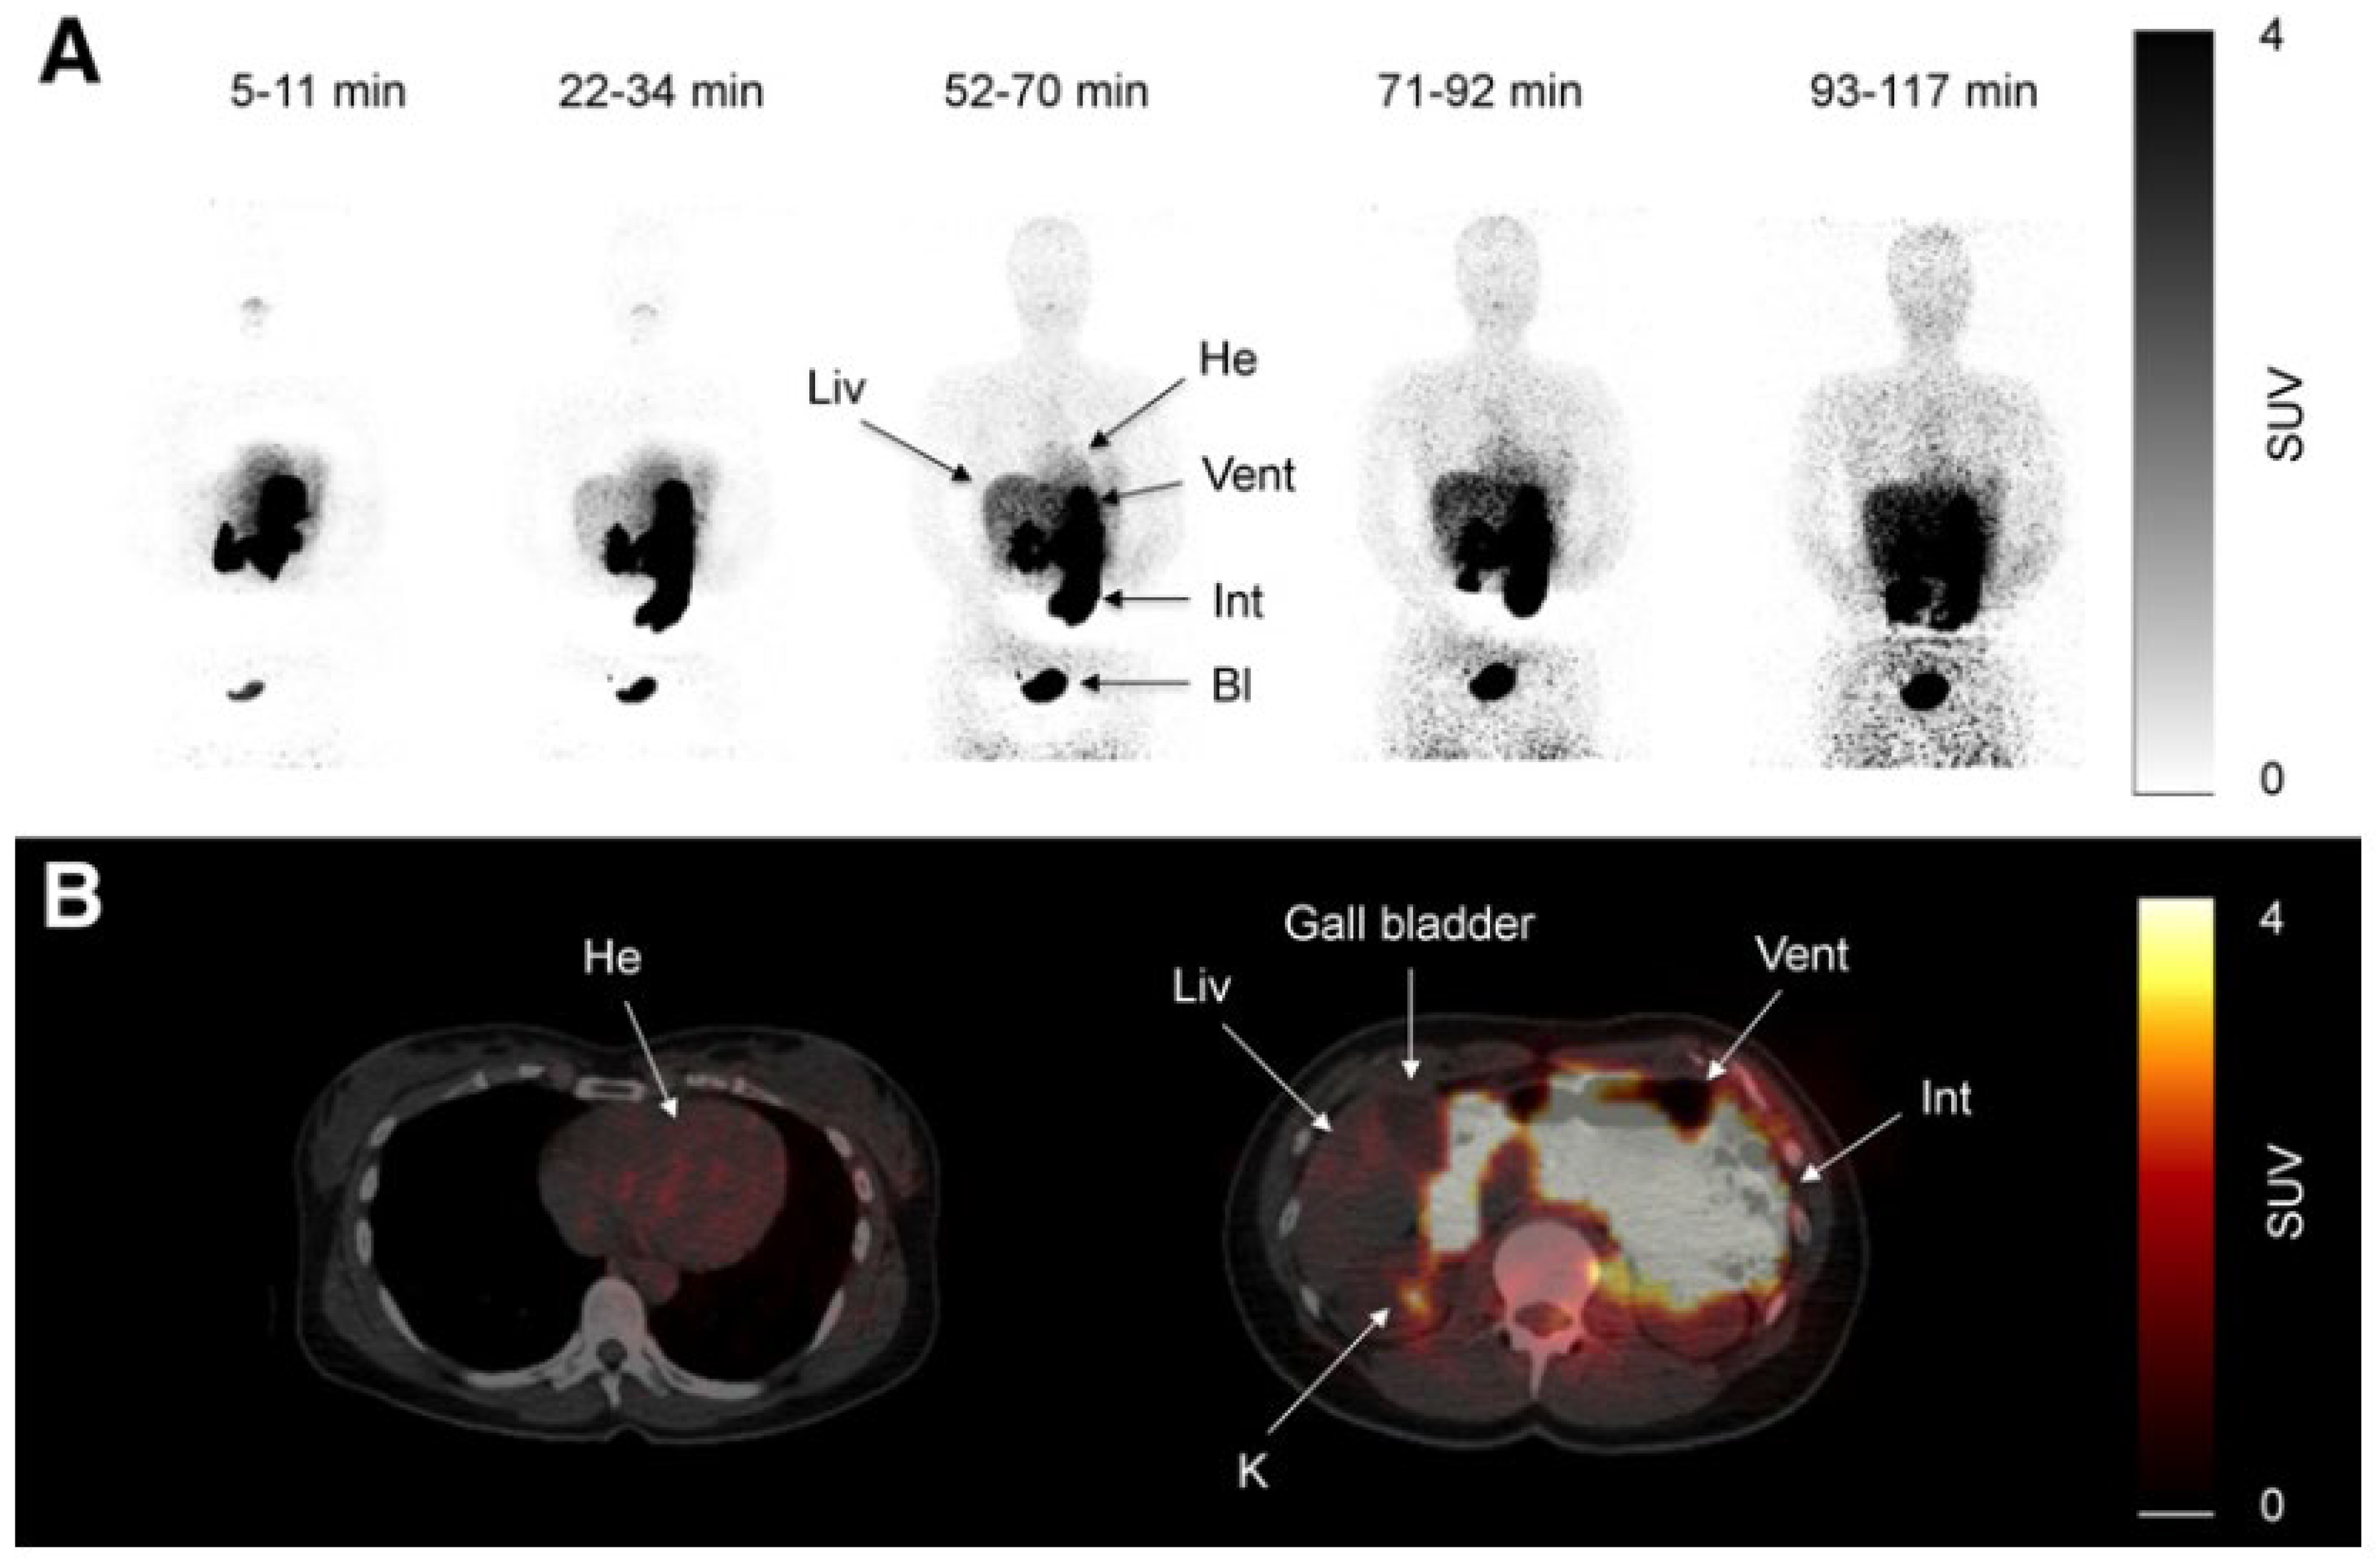

C11-metformin (9.5 microSv/MBq = ca.1.1 micrograms), first injected intravenously, allowed the study of its biodistribution in humans by the PET scan technique [133]. Most of the activity was found in the liver, the kidneys, and the urinary bladder. Most of the absorbed compound was cleared from the blood 20 min after injection. Dosimetry calculations were performed for the stomach-, small intestine-, liver-, kidney-, and bladder contents. It was demonstrated that hepatic metformin uptake is very rapid and fully reversible, but the accumulation of the activity was higher than after intravenous administration since, although slower, the tracer delivery came from the portal blood through the liver first. Two hours after the oral ingestion of the tracer, the bulk of the radioactivity was still found in the intestine (Figure 1 lower panel), and no further observation of the fate of the radioactive metformin was possible.

Figure 1.

Scans of C11-metformin administered to humans intravenously and orally (upper (A) and lower (B) panel, respectively) taken at different times after administration. Gormensen LC et al. ([133], with permission).

Although an active transport of metformin through the membrane of the hepatocyte was extensively discussed by Gromensen et al. [133], it has to be mentioned that hepatic densitometry pictures similar to those observed after intravenous and oral administration of C11-metformin can also be observed after the injection of C11-nicotine [136] or even of C11-donepezil, a high-affinity antagonist of acetylcholinesterase normally used as drug in the treatment of patients with Parkinson’s disease [137,138]. It cannot be ruled out that there is a diffusion into the space of Disse through the fenestrae of the sinusoidal endothelial cells [132] and that the compound is then washed out from the interstitium back into the hepatic vein. It may be therefore more appropriate to speak about hepatic metformin “extraction” [139] than about uptake.

The kidney-to-blood activity ratio was identical independently of the administration route of the radioactive metformin. Some discrete uptakes of the tracer was found in the salivary glands, and discrete uptake was found also in the intestine. No activity was found in the gallbladder. Significant amounts of the tracer passed to the small intestine 10 min after ingestion.